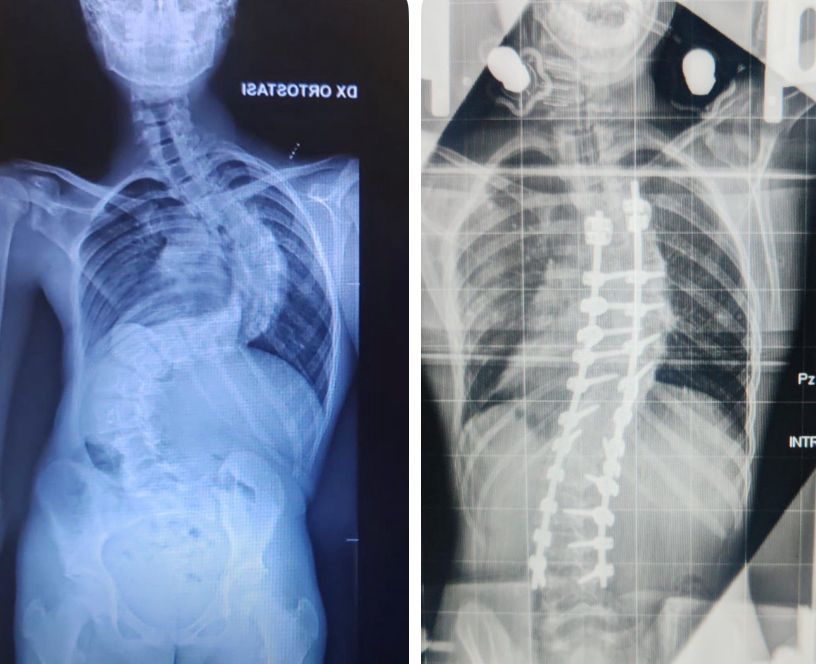

Le candeline del suo 13° compleanno le ha spente in ospedale ma il Natale potrà festeggiarlo a casa dopo oltre un mese di ricovero in ortopedia per un complesso trattamento per correggere una gravissima scoliosi di 117 gradi. L’intervento chirurgico eseguito dal dottor Andrea Piazzolla, direttore dell’unità operativa semplice a valenza dipartimentale di Chirurgia Vertebrale, gli permetterà di mettere fine a una sofferenza durata anni, con la possibilità concreta di tornare a una vita normale.

“Francesco - spiega il dottor Piazzolla - era affetto da una forma di scoliosi aggressiva, con un peggioramento impressionante: oltre 30 gradi in appena tre mesi. Una progressione rapidissima che ha imposto una preparazione preoperatoria complessa e meticolosa. Per più di un mese il ragazzo ha vissuto stabilmente in ospedale, sottoposto a trazione continua con un sistema speciale, l’halo, un dispositivo che consente di preparare progressivamente la colonna vertebrale a un intervento tanto delicato grazie al quale siamo riusciti a ridurre la scoliosi a 45 gradi”.